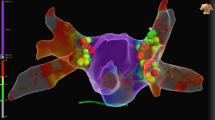

All patients underwent successful PVI. First-pass isolation was achieved in 67.5% of vein pairs (left PVs 75%, right PVs 60%). Additional ablation for early reconnection was performed in 17.5% of vein pairs (left PVs 20%, right PVs 15%). After a median waiting time of 33.5 min (IQR 22.0–45.8), all PVs were isolated without evidence of any gaps when assessed with the CMC-20 catheter. Results are presented in Table 3 and Fig. 2. Remapping with the HD Grid catheter identified a total of 6 gaps in 4 unique patients (20%). This results in 0.3 ± 0.7 gaps per patient with the HD Grid catheter versus 0 gaps with the CMC-20 catheter (p = 0.055). Two gaps were considered PV reconnection with electrograms clearly visible inside the PV, while the remaining 4 gaps showed local electrograms just within the ablation lesion set without any PV potentials visible when positioning the HD Grid catheter in the PV. Five gaps (83%) were located at the right PVs, predominantly located at the septum and carina. Only 1 gap (17%) was located at the posterior carina of the left PV. Post-ablation high-density mapping examples are presented in Fig. 3 and in cases presented as supplement 1, supplement 2, supplement 3, and supplement 4.

Post-ablation high density mapping examples. A Bipolar voltage map of a PVI with no gaps identified. A: Posterior-anterior view of a PVI procedure with no gaps identified on post-ablation HD mapping. B: Left-lateral view. C: Right-anterior view. B Case with gap at the posterior carina of the left PVs. A: Posterior-Anterior view of a bipolar voltage map showing a gap at the posterior carina of the left PVs. The sparkle map is available as supplement 3.A. B: Ablation lesions projected on the surface of the same map resulting in isolation. C: Intracardiac electrograms with the CMC-20 located in the LIPV showing entrance block. D: The HD Grid catheter showed small electrograms at the location of the gap with 2 components (lead C1-D1). First, a low frequency component corresponding to far-field atrial electrograms (white arrow). The second sharp component (red arrow) corresponds to the local electrogram and became later when moving the HD Grid towards the LIPV. E: The HD Grid catheter in the LIPV showing reconnection (red arrow). C Case with 2 gaps visualized on the bipolar voltage map. A: Two separate gaps visible at the right PVs. The first located at the anterior carina, the second gap mid-carina. B: Mid-carina electrograms visualized on the HD Grid catheter, later confirmed with the ablation catheter. C: The 2 gaps required separate ablation lesions